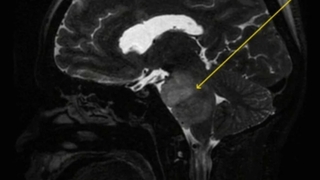

Parmakları koptu Parmakları koptu Taraklı İlçesinde elini yem makinesine kaptıran kişi yaralandı. 4 aydır hiç durmadan hıçkırıyor 4 aydır hiç durmadan hıçkırıyor Nepal'de yaşayan ve ismi açıklanmayan 30'lu yaşlarındaki Hintli bir adamın tam 4 aydır durmadan hıçkırdığı ve buna bağlı olarak bir çok sağlık sorunu yaşadığı ortaya çıktı. ABD merkezli akademik "Journal of Medical Case Reports" dergisinde yer alan habere göre, uzmanlar, ilk kez karşılaştıkları bu gizemli hastalığın nedenini bulmuş olabilir. Başkan Yüce; Sakarya kültürüyle, sanatıyla bir başka Başkan Yüce; Sakarya kültürüyle, sanatıyla bir başka AK Parti Kültür ve Sanat Kongresi’nde Sakarya Büyükşehir Belediyesi En İyi Kültür Etkinlikleri dalında ödül aldı. Bolu’da okullara 1 günlük kar tatili Bolu’da okullara 1 günlük kar tatili Bolu’da, olumsuz hava koşulları sebebiyle il genelinde okullar 1 gün süreyle tatil edildi. Yol verme kavgası kanlı bitti Yol verme kavgası kanlı bitti Kocaeli’nin Darıca ilçesinde trafikte yol verme kavgasında beyzbol sopasıyla aracından inen bir genç silahla vurularak yaralandı. Vaka sayısı 13 bine düştü Vaka sayısı 13 bine düştü Sağlık Bakanlığı'nın açıkladığı 20 Mart 2022 Pazar gününün corona virüsü (koronavirüs) tablosuna göre son 24 saatte 85 kişi hayatını kaybetti. Yeni vaka sayısında ise düne göre düşüş yaşandı. Toyota, üniversitelerle iş birliği yapacak Toyota, üniversitelerle iş birliği yapacak Toyota, Advanced Technology Acceleration Corporation (ATAC) ile araştırma ve geliştirme çalışmalarına katkı vermek adına ortak bir girişim hayata geçirdi. Uğur Akkuş tutuklanmış Uğur Akkuş tutuklanmış Ebru Şallı'nın boşanma aşamasında olduğu iddia edilen Sakaryaspor Başkan adayı eşi Uğur Akkuş hakkında şoke eden bir gerçek ortaya çıktı. Eski eşini darp ettiği için 1 yıl 7 ay 15 gün hapis cezasına çarptırılan Akkuş'un Silivri Açık Ceza İnfaz Kurumu'nda yattığı ancak Kovid-19 salgını nedeniyle cezaevinden izinli olarak ayrıldığı öğrenildi. Büyükşehir, Grand Prix yarışlarında ikinci oldu Büyükşehir, Grand Prix yarışlarında ikinci oldu Manavgat ve Side de gerçekleştirilen ve 10 kıtadan 24 takımın yarıştığı Grand Prix yarışlarında Büyükşehir Belediyesi Sporcusu Mykhaylo Kononenko ikincilik elde etti. Spor Yasası, TBMM'ye sunuluyor Spor Yasası, TBMM'ye sunuluyor Sporda büyük değişim başlıyor. Spor Yasası bu hafta Türkiye Büyük Millet Meclisi'ne sunulacak. Yasa onaylanırsa bundan sonra kulüp başkanları borçlardan sorumlu olacak. Türkiye Güreş Şampiyonası’ndan madalya ile döndüler Türkiye Güreş Şampiyonası’ndan madalya ile döndüler Büyükşehirli güreşçiler, U20 Grekoromen Güreş Türkiye Şampiyonası’nda 5 madalya kazandı. Arkadaş katili tutuklandı Arkadaş katili tutuklandı İlçesinde kıraathanede oyun oynadıkları esnada arkadaşını silahla vurarak öldüren şahıs tutuklandı. Sakaryaspor 2 Adıyaman FK 0 Sakaryaspor 2 Adıyaman FK 0 Lider Sakaryaspor, sahasında Adıyaman FK'yı 2-0 mağlup etti. Down sendromlu milli yüzücü, şampiyon sporcular yetiştirmek istiyor Down sendromlu milli yüzücü, şampiyon sporcular yetiştirmek istiyor Katıldığı şampiyonalarda başarılarıyla adından söz ettiren down sendromlu milli yüzücü Fatma Çağla Demir, yüzme antrenörü olup kendisi gibi şampiyon sporcular yetiştirmek için müsabakalar dışında üniversite sıralarında da ter döküyor. Minibüsü arızalanan sürücünün yardımına trafik polisi koştu Minibüsü arızalanan sürücünün yardımına trafik polisi koştu Hendek ilçesinde devriye gezen trafik polisi, yolda kalan sürücüye, arızalanan minibüsünü akaryakıt istasyonuna kadar iterek yardımcı oldu.